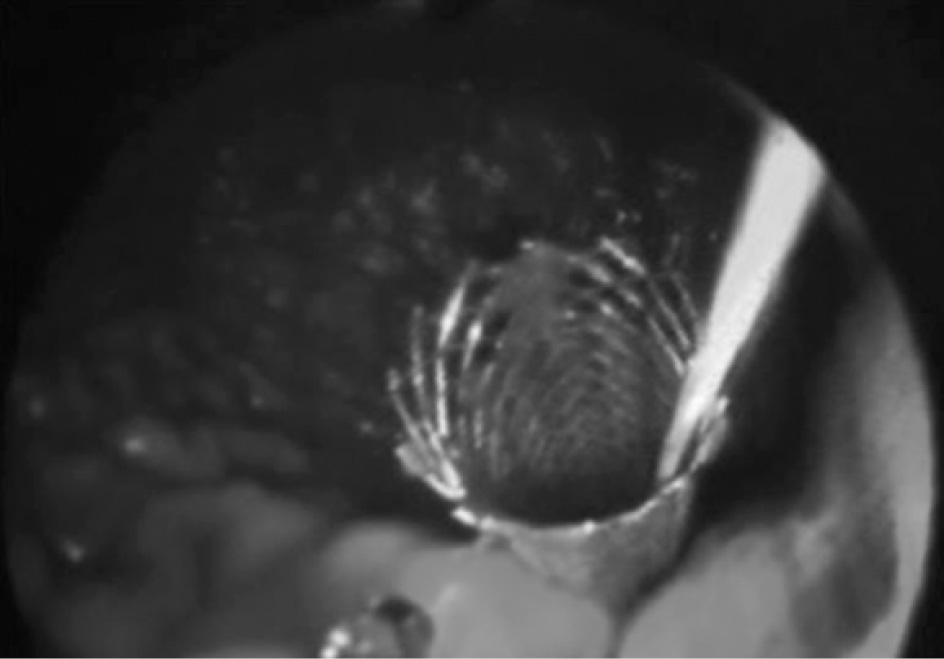

В 7 случаях пациентам с постнекротическими кистами, содержащими секвестры, выполнено эндоскопическое цистогастральное стентирование с использованием металлического покрытого саморасширяющегося стента диаметром 10 мм (рис. 2, 3), с временной установкой санационного цистоназального катетера через просвет стента.

Рис. 2. Фотография при эндоскопии. В просвете желудка визуализируется саморасширяющийся покрытый металлический стент и установленный через его просвет цистоназальный дренаж